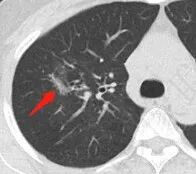

右上叶磨玻璃影,有结节感,首先考虑结核,类似于烟花征

烟花征,tb

影像特点:右肺上叶混合磨玻璃影,边界清晰,结构松散,内有多结节堆积及支气管扩张影,可见小叶间隔增厚,并局部增厚的小叶间隔上亦存在微结节,胸膜侧可见纤细索条,病灶周围可见多发微结节影。

总体分析:从病灶分布来看符合结核的好发位置,影像表现也符合结核的多态性,且出现卫星灶。由于有边界清晰的GGO,需要鉴别腺癌,虽然此病例有边界清晰的GGO,但是它的GGO的边缘有结节感,呈多结节堆积,而腺癌的GGO缺乏这种“多结节堆积感”,另外,此病例也没有发现腺癌的胸膜凹陷征、毛刺征及月牙铲等。

1、年轻人多见,一般提示免疫力可能有下降。 2、好发部位与其它结核类似,上叶及下叶背段为主。 3、烟花征,反晕征,环呈结节状,可以伴随空洞,树芽征,结节灶,胸水。(反晕征:一般周围实性环形高密度影,中央丛密度低;一般环超过圆的3/4,结核的环主要是小叶核心结节组成,类似于多发树芽征聚集,边缘结节感。中央的晕:可以是腺泡结节,树芽征,细网状,磨玻璃影,很少正常,主要成分是小叶内间质增厚、小叶核心结节、肺泡内病变。)其实也体现了结核的多灶性、多态性特点。

4、其实不一定完全表现为反晕征,还有比较密集的烟花,聚集成团,与反晕征同在。